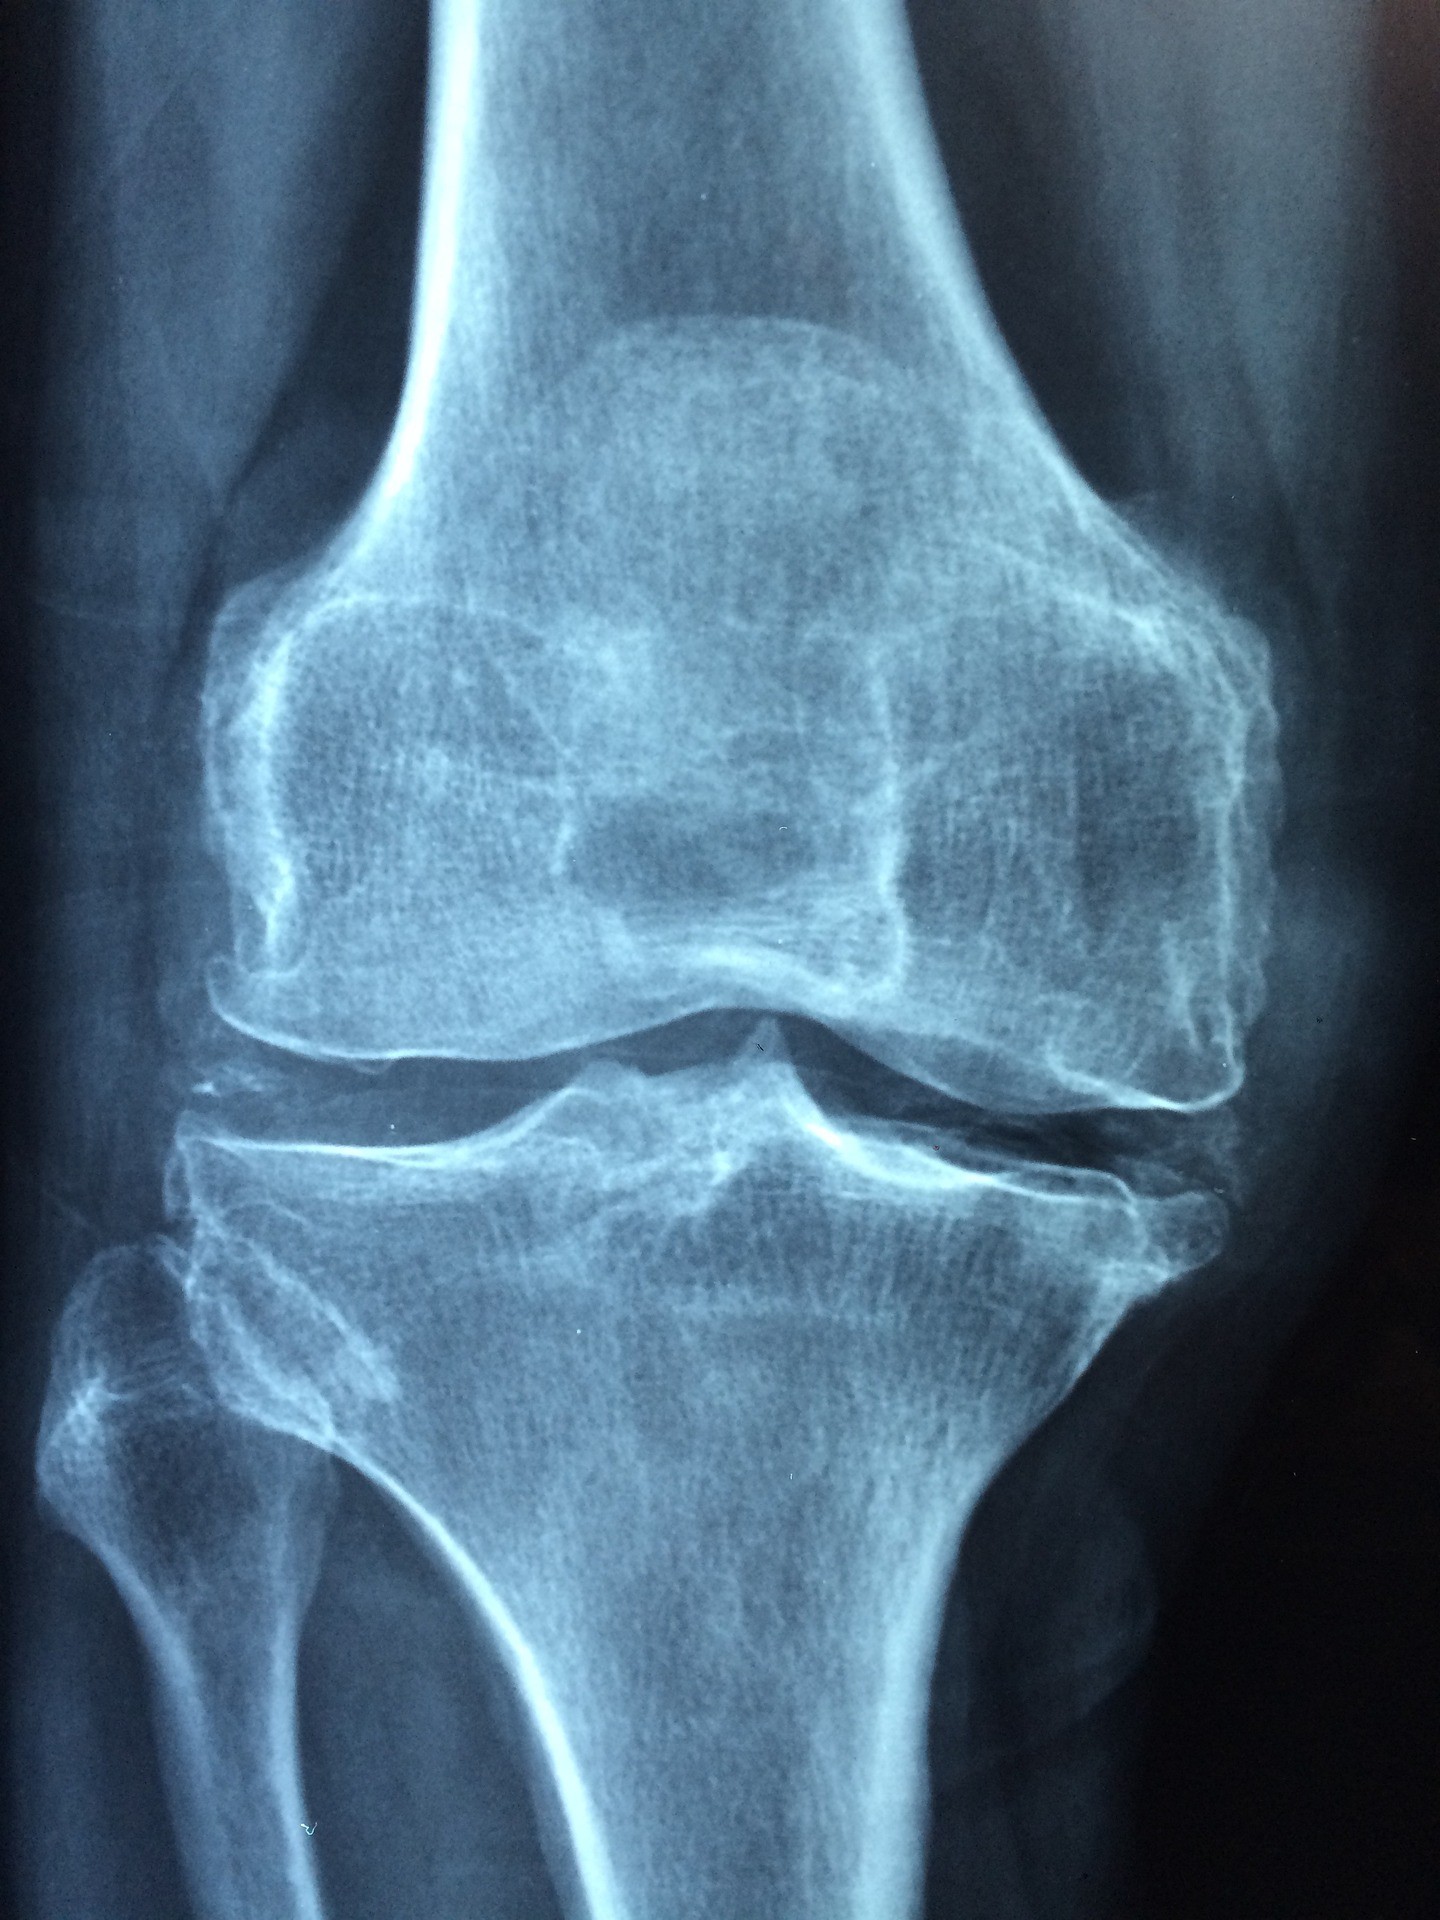

Osteoporose - auch Knochenschwund genannt - ist eine Krankheit, bei der die Knochendichte und -struktur im Verlauf der Zeit immer weiter nachlässt. Zu Beginn bleibt die Krankheit oft unbemerkt, da sie ohne große Schmerzen oder Probleme einhergeht. Im Laufe der Zeit kommt es jedoch vermehrt zu (komplizierten) Knochenbrüchen, Schmerzen und einer eingeschränkten Mobilität.

Falls familiär oder durch sonstige Lebensumstände ein erhöhtes Osteoporose-Risiko vorliegt, kann eine regelmäßige Knochendichtemessung helfen, den Zustand der Knochen zu überwachen und frühzeitig Maßnahmen zu ergreifen. Die Knochendichtemessung geschieht mittels Röntgenstrahlung an der Lendenwirbelsäule oder am Oberschenkelknochen. Die Kosten trägt die Krankenkasse, wenn ein Befund für Osteoporose vorliegt.